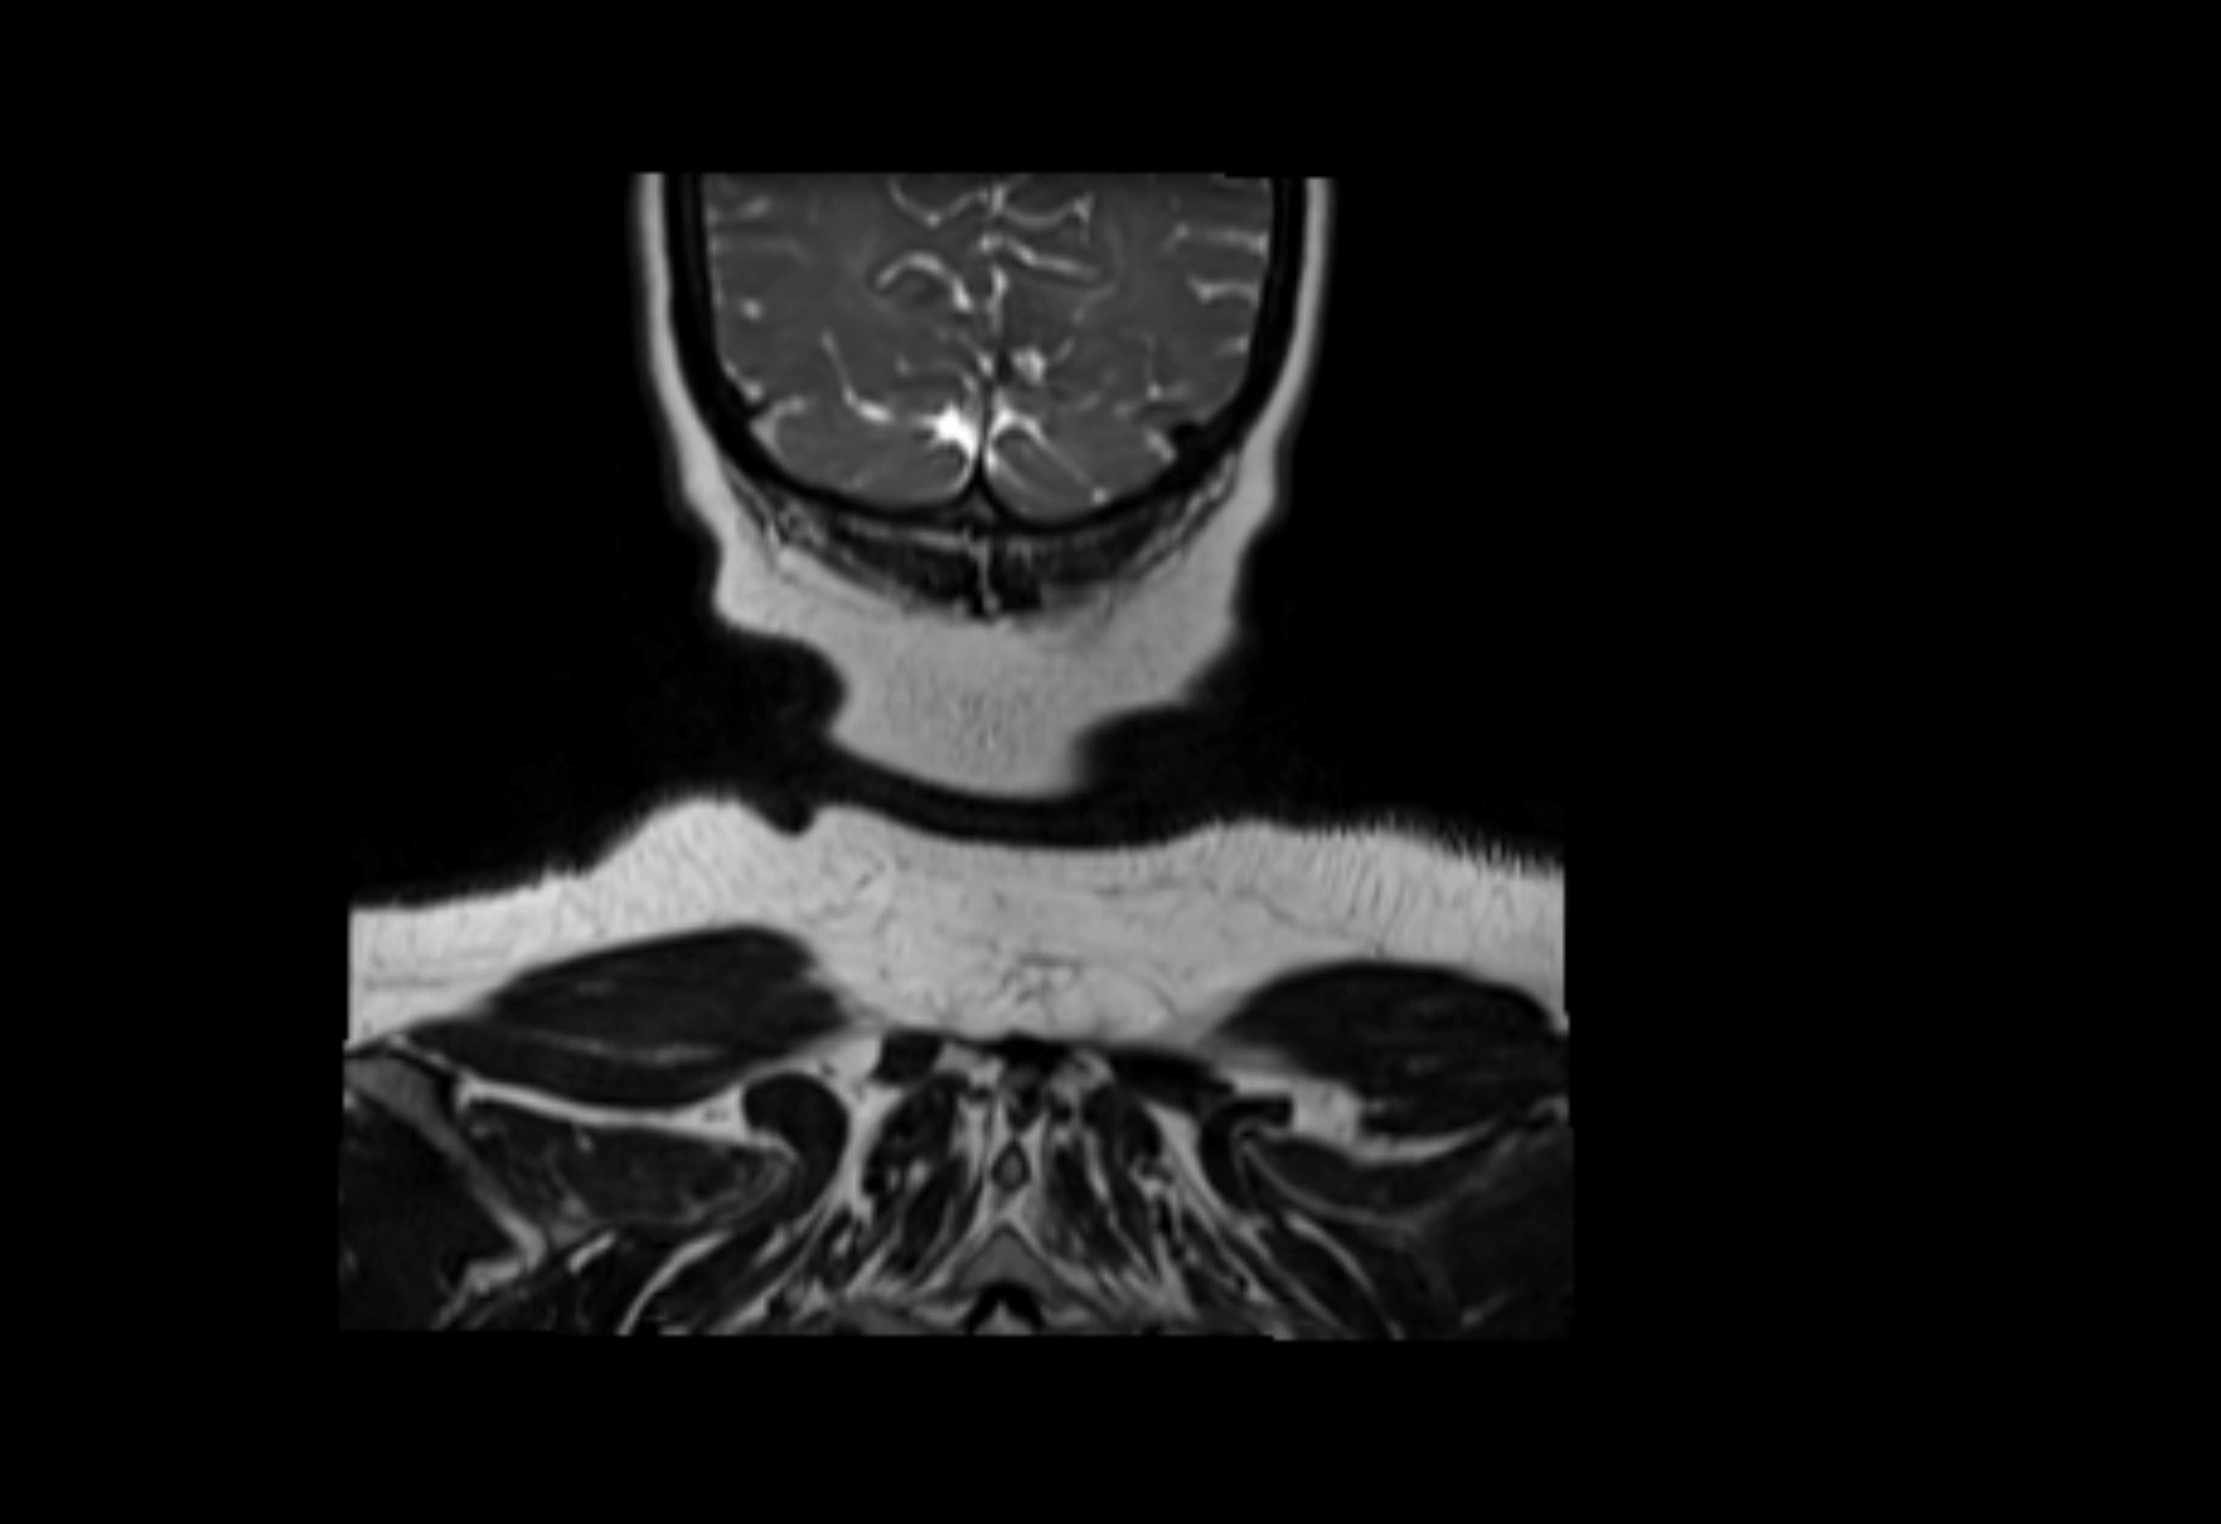

MRI Appearance

T1-weighted images:

• Normal accessory nodes appear as small, oval hypointense to intermediate signal structures within subcutaneous fat

• Surrounded by hyperintense fat, enhancing contrast for visualization

• Pathological nodes may appear enlarged or rounded, sometimes with cortical thickening

T2-weighted images:

• Nodes show intermediate signal, with surrounding fat bright

• Useful for detecting edema, inflammation, or infiltration

• Fatty hilum may appear slightly hyperintense relative to cortex

STIR (Short Tau Inversion Recovery):

• Fat suppression enhances visualization of edematous or pathological nodes

• Normal nodes appear low to intermediate signal, while inflamed or metastatic nodes appear hyperintense

• Useful for detecting subtle lymphadenopathy or early pathology

MRI images

image